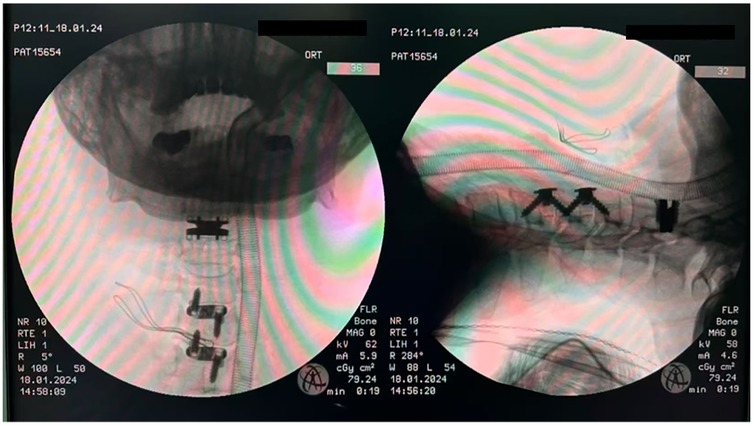

Background Cervical disc herniation at the C2-3 level, resulting in cervical spondylotic myelopathy (CSM), is an uncommon clinical entity. The diagnostic and therapeutic complexity escalates when this pathology coexists with non-contiguous multilevel cervical disc degenerative disease (CDDD). Due to the segmental variability in pathological features, the clinical manifestations of such cases are highly heterogeneous, thereby necessitating a highly individualized treatment strategy. Hybrid surgery (HS), which integrates cervical disc arthroplasty (CDA) and anterior cervical discectomy and fusion (ACDF), offers a tailored approach for the management of multilevel degenerative cervical pathology. The unique anatomical features and surgical technical challenges at the C2-3 level impose significant constraints on treatment options. This article presents a case of non-contiguous three-level hybrid surgery involving CDA at C2-3 and ACDF at C4-5 and C5-6, and discusses the feasibility of this technique for upper cervical disc pathology. Case Presentation A 62-year-old female was admitted with a 6-month history of neck and right upper limb pain, numbness, and gait instability, which had been unresponsive to conservative management. DR revealed loss of the normal cervical lordosis. CT showed no significant osteophyte formation or bony canal stenosis. MRI demonstrated a large disc extrusion at C2-3 causing spinal cord compression, and disc herniations at C4-5 and C5-6 with nerve root impingement. Based on clinical and imaging findings, a diagnosis of multilevel cervical spondylopathy (C2-3, C4-5, and C5-6 disc herniation) was established. The patient underwent anterior cervical discectomy followed by artificial disc arthroplasty (CDA) at C2-3, and anterior cervical discectomy and fusion (ACDF) at C4-5 and C5-6, successfully completing a non-contiguous three-level hybrid surgical procedure. Results Postoperative symptoms were significantly alleviated. At the 12-month follow-up, pain and gait disturbance had largely returned to normal. MRI confirmed adequate decompression of neural compression, DR demonstrated satisfactory range of motion (ROM) at C2-3, and CT revealed satisfactory bone healing at the fused segments. Conclusion CDA serves as an effective alternative for C2-3 disc pathology, achieving neural decompression while preserving segmental mobility. The HS provides a valuable surgical option for the precise treatment of non-contiguous multilevel degenerative disease.